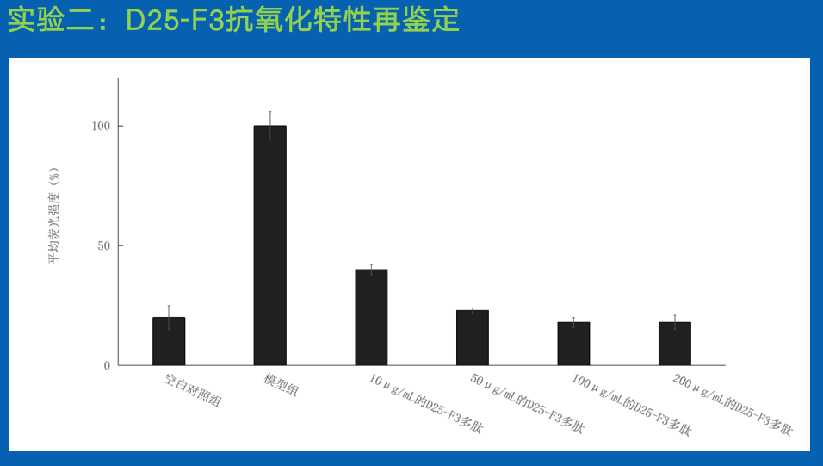

实验一:抗氧化多肽活性鉴定

结论:

SEQ ID NO:1的多肽D25-F3具有更强的抗氧化特性,与SEQ ID NO:2多肽 D25-F7相比针对DPPH清除能力以及ABTS的清除能力均显著提高(P<0.01)。

结论:

实验结果表明多肽具有对H2O2诱导的HDF细胞损伤具有保护作用,并且随着浓度的增加保护效应逐渐提高,且有剂量依赖性,在100μg/mL的多肽浓度下,荧光强度低至(18.26±1.43)%,显著的低于模型组的(99.86±5.97)%。